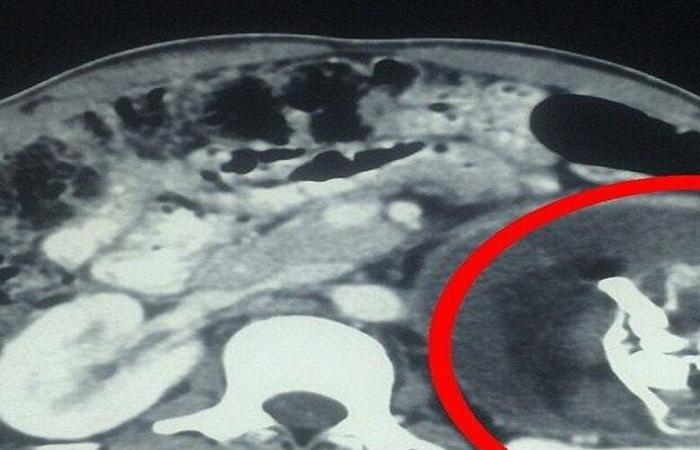

وفقا لما نشرته صحيفة Need To Know فإن مستشفى كابول استقبل طفلا يعاني من انتفاخ في البطن. واشتبه الأطباء أولا بإصابته بورم "ويلمز" (ورم كلوي) يظهر أحيانا لدى حديثي الولادة. لكن الفحص بالأشعة كشف وجود تكوين في تجويف البطن يضم أنسجة رخوة، من الدهون والسوائل والبنية العظمية".

وتمكن الأطباء من التعرف على عظام وجه متكونة، وعمود فقري، وأضلاع في الصورة.

ونجح الجراحون في إجراء العملية واستخراج الجنين الطفيلي غير المكتمل، الذي بلغ حجمه 8× 12 سنتيمترا.